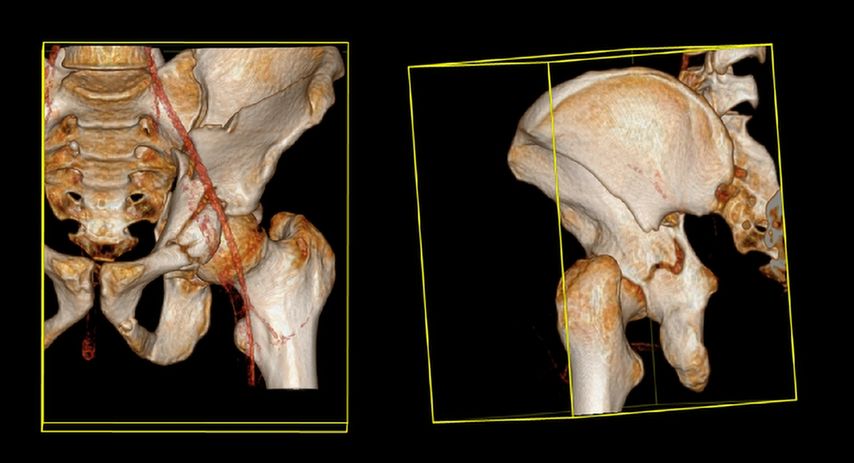

Die Mehrheit der Herausforderungen bei der Behandlung der Fragilitätsfraktur des Acetabulums überschneidet sich mit denen bei Beckenringfraktur. Ebenso wenig überraschend treten auch auf der anderen Seite des Hüftgelenkes ähnliche Komplikationen und eine Reduktion der Lebenserwartung wie bei hüftnahen Oberschenkelfrakturen auf. Im Unterschied zu den FFP gilt dieselbe Klassifikation für Hochrasanz- und Niedrigenergietraumata des Acetabulums nach Judet und Letournel. Der große Unterschied besteht jedoch in der Häufigkeitsverteilung. Aufgrund der meist einfachen Stürze mit Gewalteinwirkung über den Trochanter major betreffen die Fragilitätsfrakturen des Acetabulums meist den vorderen Pfeiler und die quadrilaterale Fläche. Entsprechend sind dislozierte Frakturen eine Domäne der offenen Operationsverfahren und der Hüftendoprothetik. Der Stellenwert der minimalinvasiven Stabilisierung nicht dislozierter Acetabulumfrakturen und der Stabilisierungen in Fehlstellung ist wissenschaftlich nicht geklärt. Jedoch gibt es zunehmende Literatur über das sogenannte „fix and replace“, bei dem eine Osteosynthese eines Pfeilers mit einer primären Totalendoprothese in einer Operation kombiniert wird (Abb. 2).

Abb. 2: „Fix and replace“ mit Osteosynthese und Hüfttotalendoprothese in der selben Operation bei geriatrischer Acetabulumfraktur mit Impressionsfraktur des Doms

Bisher konnten dabei keine erhöhten Komplikationsraten gegenüber der konventionellen Osteosynthese festgestellt werden. Gleichzeitig besteht aber der Vorteil der Vollbelastbarkeit, des Einsatzes einer konventionellen Pfanne und der in der Orthogeriatrie erwünschten „one-shot surgery“ (nur eine Operation statt einer potenziellen zweiten Operation bei Versagen der Osteosynthese und sekundärer Prothese). Bei ca. 30% der geriatrischen Acetabulum-Osteosynthesen in der Literatur erfolgte eine Revision mittels Prothese. Risikofaktoren für die Notwendigkeit einer sekundären Hüfttotalendoprothese nach Osteosynthese sind: höheres Alter, Impressionsfrakturen des Doms und Hüftkopfes, Medialisierung des Hüftkopfes („zentrale Hüftluxation“), nichtanatomische Reposition (häufig durch späte Versorgung nach konservativem Therapieversuch oder längerer Operationsvorbereitung bei Multimorbidität).

Im Gegenzug dazu wird in der Literatur auch eine minimalinvasive offene Osteosynthese beschrieben, wobei man auf ausgedehnte Repositionsmanöver mit dem damit verbundenen Blutverlust verzichtet. Dadurch werden zum Teil verbliebene Fehlstellungen akzeptiert bzw. wird durch postoperative Mobilisierung eine sekundäre Dislokation in Kauf genommen, um eine postoperative Vollbelastung zu ermöglichen. Eine entsprechende Operationstechnik über einen Stoppa-Zugang und mit Plattendesign mit Abstützung der quadrilateralen Fläche wurde durch Culemann 2023 anschaulich beschrieben.12 Bei geschwächter Knochenqualität ist neben dem Plattendesign mit medialer Abstützung an der quadrilateralen Fläche auch das Augenmerk auf eine stabile Verankerung zu legen. Die infraacetabuläre hintere Pfeiler-Schraube, welche meist um die 100mm Länge aufweist, ist hierbei sehr empfehlenswert (Abb. 2 und Culemann 202312).